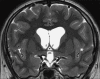

Background: Colloid cysts are usually located at the rostral part of the third ventricle in proximity to the foramina of Monro. Some third ventricular colloid cysts, however, attain large sizes, reach a very high distance above the roof of the third ventricle, and pose some challenges during endoscopic excision. These features led to the speculation that for such a pattern of growth to take place, the points of origin of these cysts should be at areas away from the foramina of Monro at which some anatomical "windows" exist that are devoid of compact, closely apposed forniceal structures.

Results: Colloid cysts may grow vertically up past the roof of the third ventricle through anatomical windows devoid of the mechanical restraint of the forniceal structures.

Conclusion: Some anatomical variations of the forniceal structures may allow unusually large sizes and superior vector of growth of a retro- or post-foraminal colloid cyst. Careful preoperative planning and knowledge of the pertinent pathoanatomy of these cysts before endoscopic excision is very important to avoid complications.